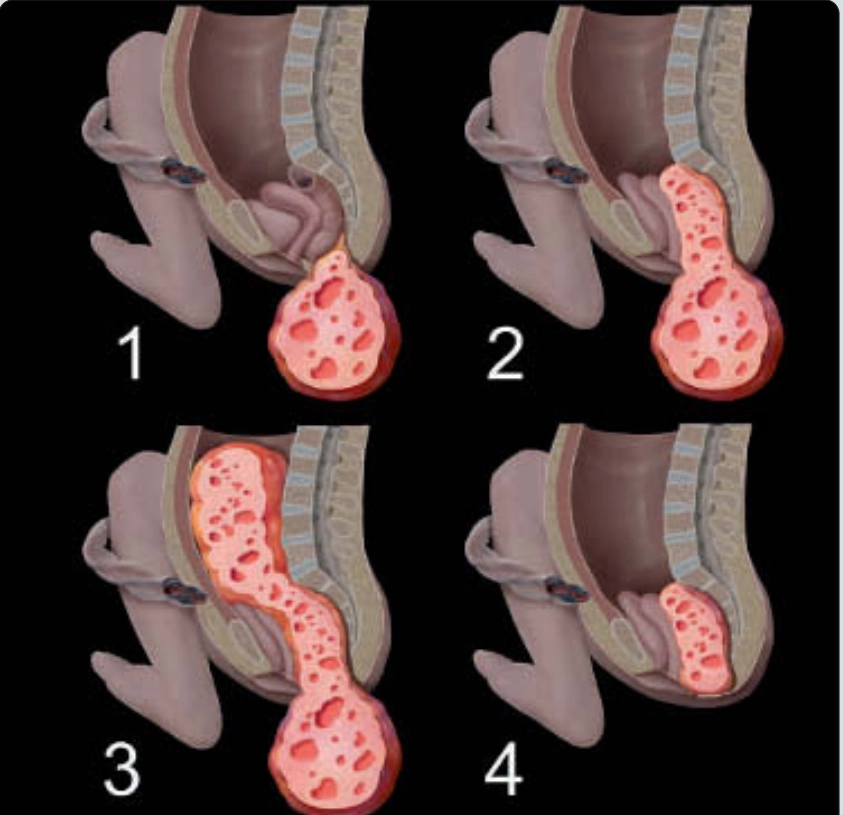

U quái vùng cùng cụt (Sacrococcygeal Teratoma)

• U quái vùng cùng cụt (Sacrococcygeal Teratoma)